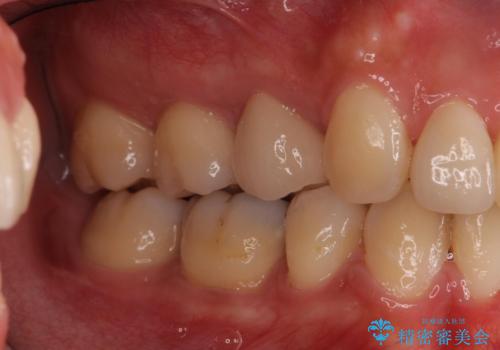

重度のがたつき 矯正治療+セラミック治療で綺麗な歯並びに 矯正専門では難しい治療

- 歯並びを気にして来院。

乳歯が残存しており、また左上の犬歯もずれて生えてきていました。

右上の前歯も細長い特殊な形をしていました。(矮小歯といいます)

矯正治療で歯並びを治した後、乳歯を抜いたところにブリッジを入れています。

左上の奥歯はすれ違っていたためそのかみ合わせも整えています。

歯を抜いて治療を行ったため、Eラインが整った形で治療ができました。口が断然閉じやすくなっています。